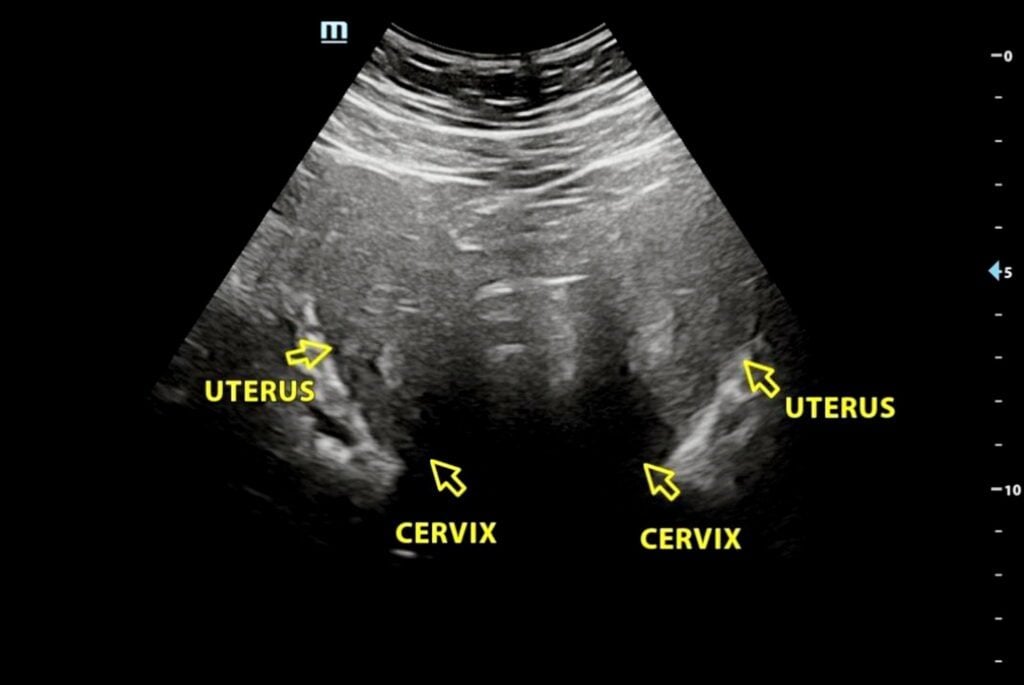

艾莉的患病真相在一次意外中露出端倪。她19岁时因腹痛疑似盲肠炎送院,虽然手术证实阑尾并无大碍,但医生却在其腹腔内意外发现疑似有两个子宫。尽管后续进行了多次扫描,但由于成像模糊,院方始终无法定论其属于子宫完全分裂的“双子宫”,还是顶部凹陷的“双角子宫”。

在经历每年进出急诊室三、四次的痛苦折磨后,艾莉终于在2025年12月通过腹腔镜手术揭开了谜底。诊断证实,她患有“完全性双角子宫”,并拥有两个独立的子宫颈。更棘手的是,她同时患有严重的子宫内膜异位症,异位组织不仅缠绕着肠道,甚至导致肠道卡在两个子宫之间,因剥离风险过高,医生当时被迫放弃切除手术。